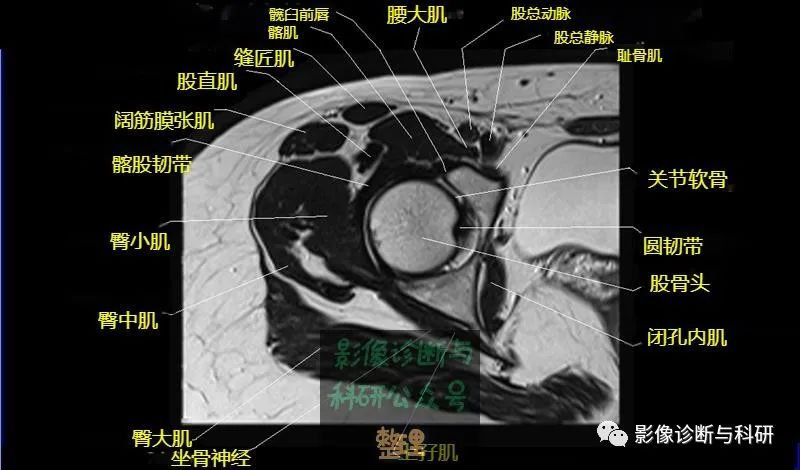

髋关节MR轴位详细标注

大腿肌配布于股骨周围,分前、后和内侧三群

前群

位于大腿前面,有缝匠肌和股四头肌。

内侧群

位于大腿内侧,共5块,其中股薄肌位于最内侧;另4块分三层,浅层靠外上方为为耻骨肌,下方为肌长收肌。长收肌深面是第二层的肌短收肌。第三层是强有力的大收肌。这一群肌均起自耻骨支和坐骨支,除股薄肌止于胫骨上端内侧外,其余各肌都抵止在股骨粗线。

后群

位于股骨后方,包括股二头肌、半腱肌和半膜肌。